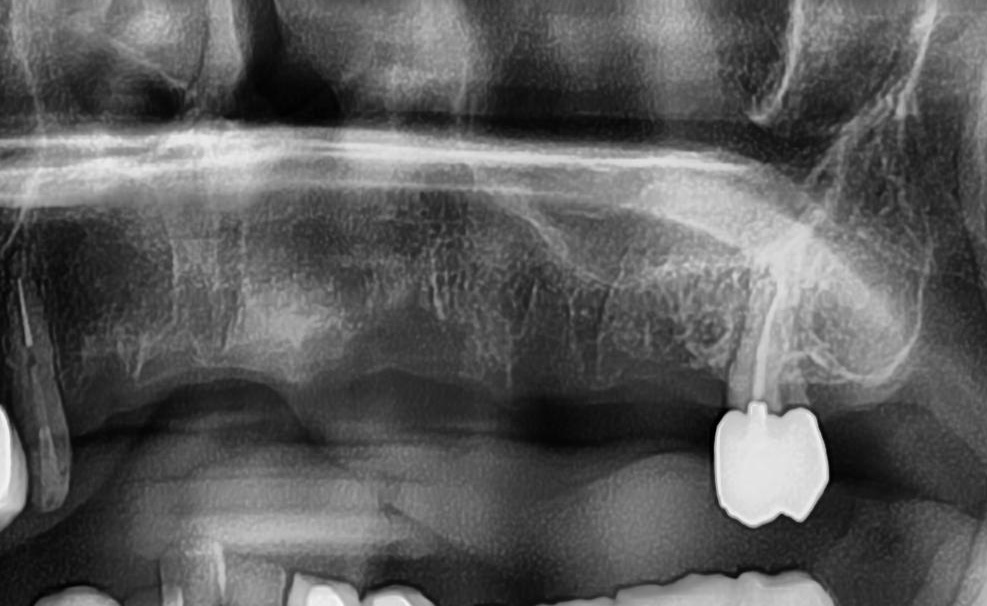

今回の患者様は、以前にもインプラントを植立された経験がある方で、今回もインプラント植立を希望されたので、右上1番目・2番目、左上1番目、2番目~6番目の合計7本の植立が決まりました。

しっかりとインプラント埋め込まれた後は、動揺がないか、噛んだ時に当たらないかなどを確認して、最後にパノラマ写真を撮影して今回のオペは終了となりました。